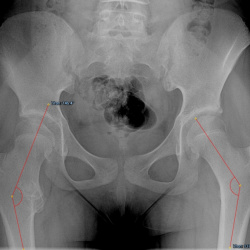

06.09.2024 - 09:56

Здравствуйте, пациентам 65 лет, скажите есть ли тут признаки нестабильности эндопротезов?